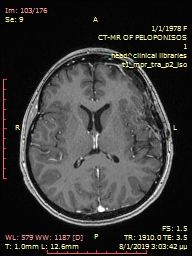

Preoperative large brain meningioma.

Pre-operative ectopic cerebral meningioma.